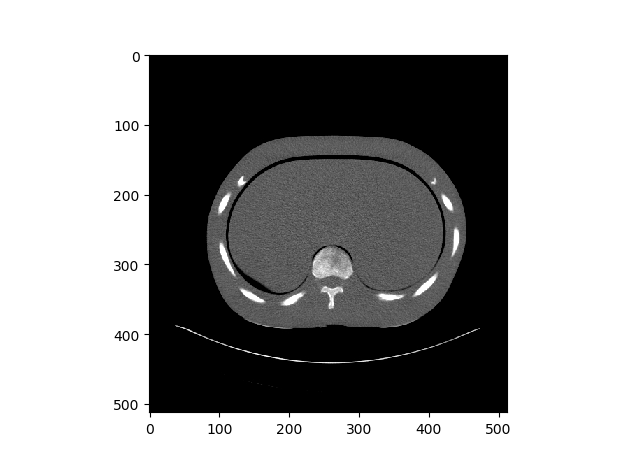

Case 1: Training and Results

Case 1 was normal stochastic gradient descent, as seen above, the overall shape of the CT Scan can be seen. However it is very hard to see. Right image is one of original image for comparison.

Case 2: Training and Results

For gradient noise, you can kinda? see something in the middle. However there is no way to tell that this was a Lung CT Scan image. Right image is one of original image for comparison.

Case 3: Training and Results

Now with Dilated Back Propagation, we can see that the resulted denoised images look very similar to the case 1 results. However, again very hard to tell exactly which is the lung part of the CT Scan. Right image is one of original image for comparison.

Case 4: Training and Results

Now we can clearly see what we are looking at. However it lacks details, and I mean A LOT of details. If you compare the GIF with the right image, you can barely make out the details. Right image is one of original image for comparison.